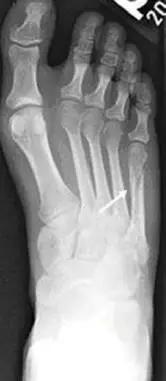

13. Lisfranc 骨折

骨折累及到足的跗骨关节。跖跗关节位于足的前部,是构成足纵弓及横弓的重要结构。

第一跖骨与第一楔骨组成鞍状关节,整个跖跗关节的稳定性,有赖于第一跖跗关节的稳定性,一旦第一跖跗关节发生脱位,其他 4 个跖跗关节容易发生脱位。第一跖跗关节的关节囊有背侧和跖侧副韧带增强,其内缘尚有胫前肌腱附着。第一、二跖骨基部无韧带相连,第一楔骨与第二跖骨基部间有坚韧的 Lisfranc 韧带相连,有助于第一跖跗关节的稳定性。第二楔骨较短,第二跖骨位于第一、二楔骨之间成为外力作用的支点。因此第二跖骨基底易发生骨折。

Lisfranc 关节复合体(Lisfranc joint complex)示意图:first metatarsal 第一跖骨;second metatarsal 第二跖骨;Lisfranc joint 利斯弗朗关节;first,second and third cuneiforms 第一,二,三楔骨;cuboid 骰骨

14.第五跖骨骨折

第五跖骨基底部骨折的不同类型:Stress 骨折;Jones 骨折:第五跖骨基底部以远 1 英寸内的骨折称为 Jones 骨折; Avulsion 骨折。

(来源:Radiopaedia)

Stress 骨折(来源:OrthoInfo-AAOS)

Jones 骨折正位片(来源:Radiopaedia)

Jones 骨折斜位片(来源:Radiopaedia)